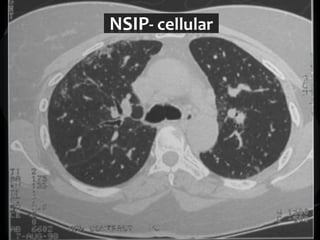

Reticular Pattern - NSIP

inflammation and fibrosis

 Predominantly basilar

 Significant ground glass

 Subpleural sparing low sensitivity, high specificity

 No honeycombing, some cystic change

 Traction Bronchiectasis

Diagnostic accuracy 50%

 Cellular NSIP

 Fibrotic NSIP

 Associated with CVD

 Undifferentiated CVD – T. King

NSIP- cellular

NSIP-fibrotic